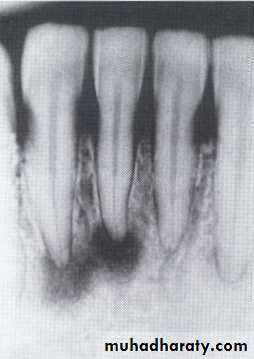

Multiple but separated radiolucent lesions

• Hyperparathyroidism

Increased secretion of parathormone, causes generalized skeletal bone resorption leading to osteopenia (generalized decrease in bone density).Single or multiple radiolucency in the maxilla & mandible.

• Loss of normal bone trabeculation & replaced by fine poorly calcified bone spicules that give ground glass appearance.

• Missing of lamina dura.

• D.D.by elevation of serum calicum & alkaline phosphatase levels.

Loss of the lamina dura and the granular texture of the bone pattern.